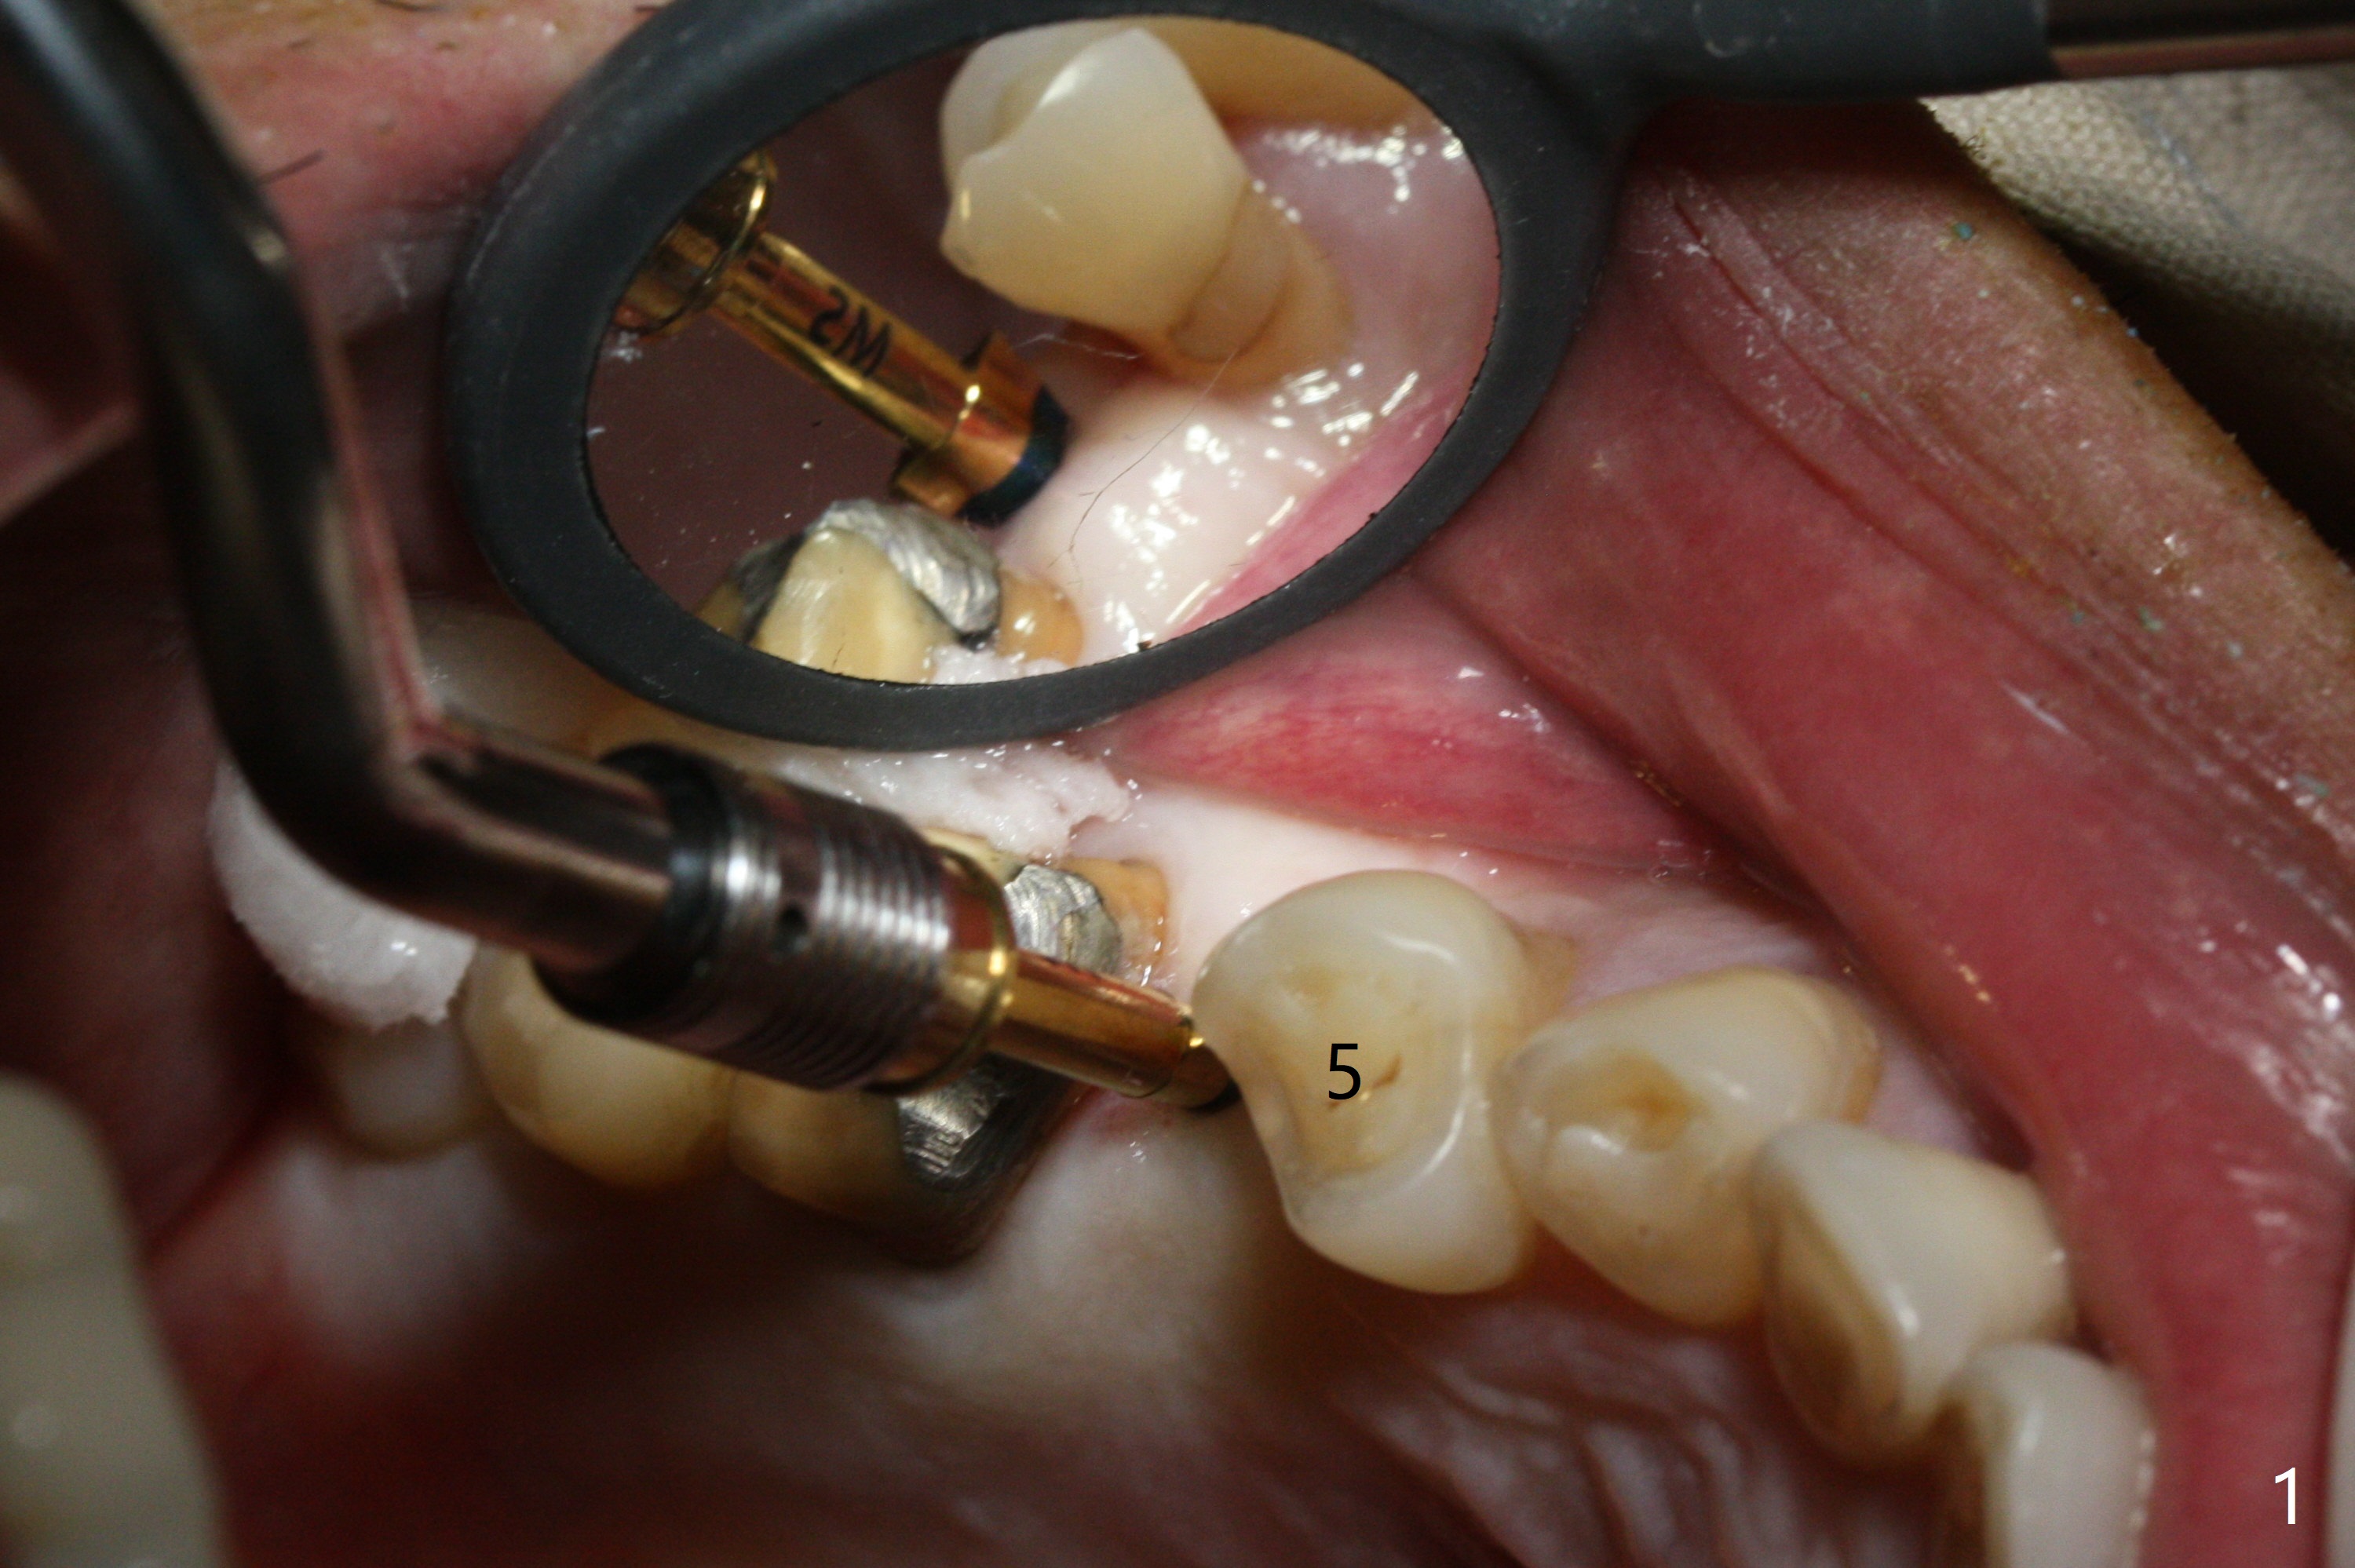

As planned, osteotomy starts at #4 prior to #3 extraction (Fig.1,2). In fact the bone density at the edentulous area is high. Drills are used to finish placing a 4x17 mm tissue-level implant (Fig.3).